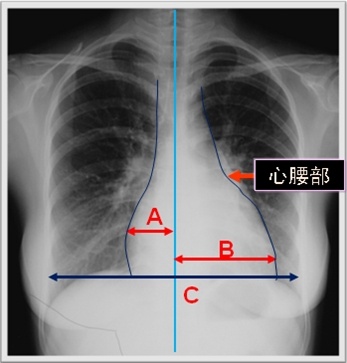

可如何判斷心臟的大小呢?

主要根據(jù)心胸比例

心胸比例=〔(A+B)/C〕<0.5

輕度增大=0.51~0.55

中度增大=0.56~0.60

重度增大>0.60